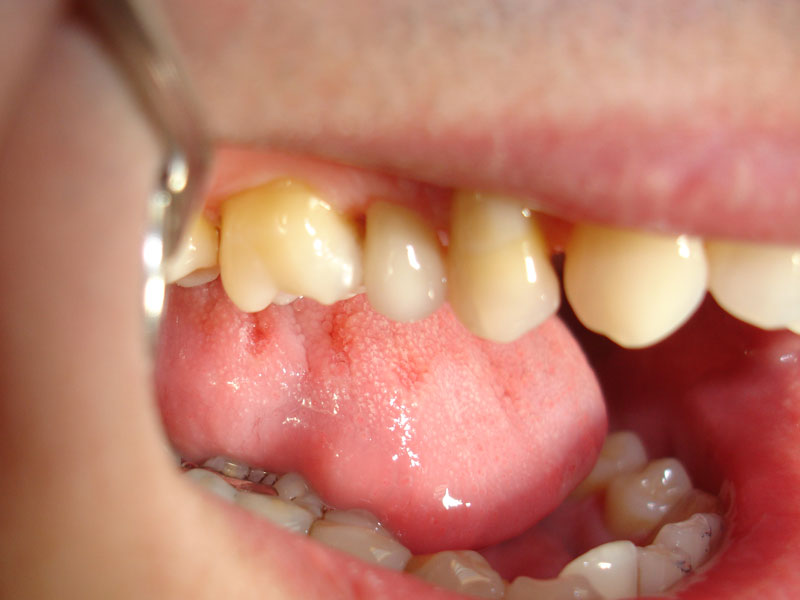

Prin tratamentul cu implanturi dentare se asigura refacerea arcadelor dentare atunci cand nu se doreste devitalizarea si slefuirea unor dinti, sau atunci cand nu sunt suficienti dinti pe care sa poata fi realizata o restaurare protetica fixa.